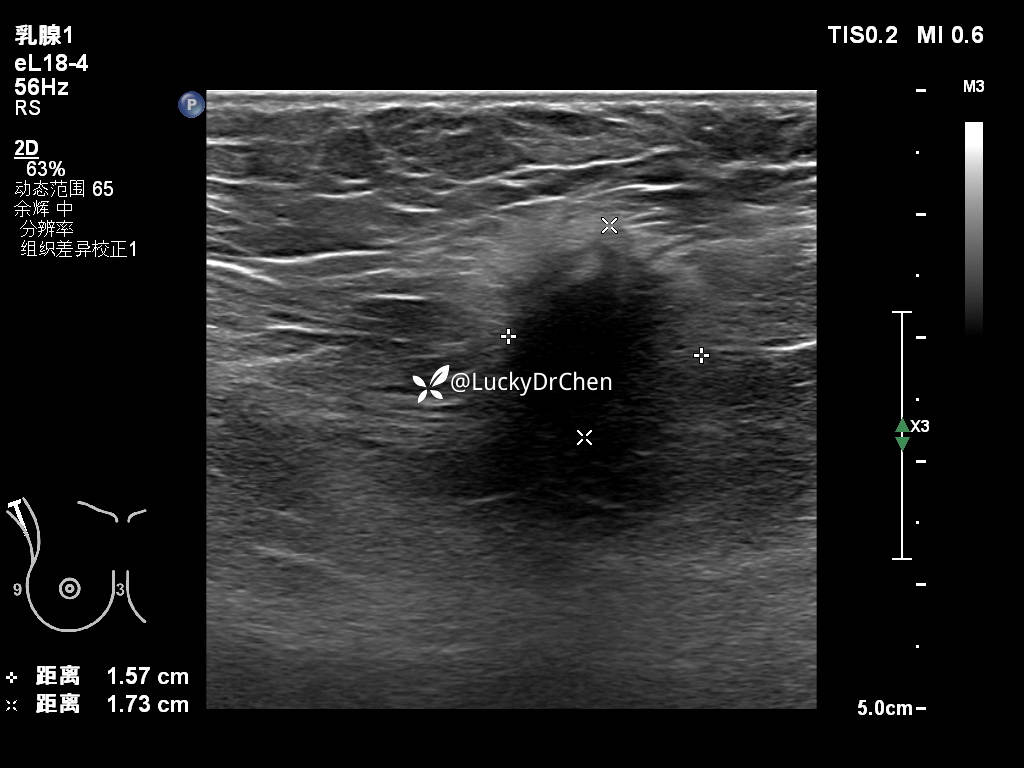

斑丘的超声表现:皮肤层低回声区